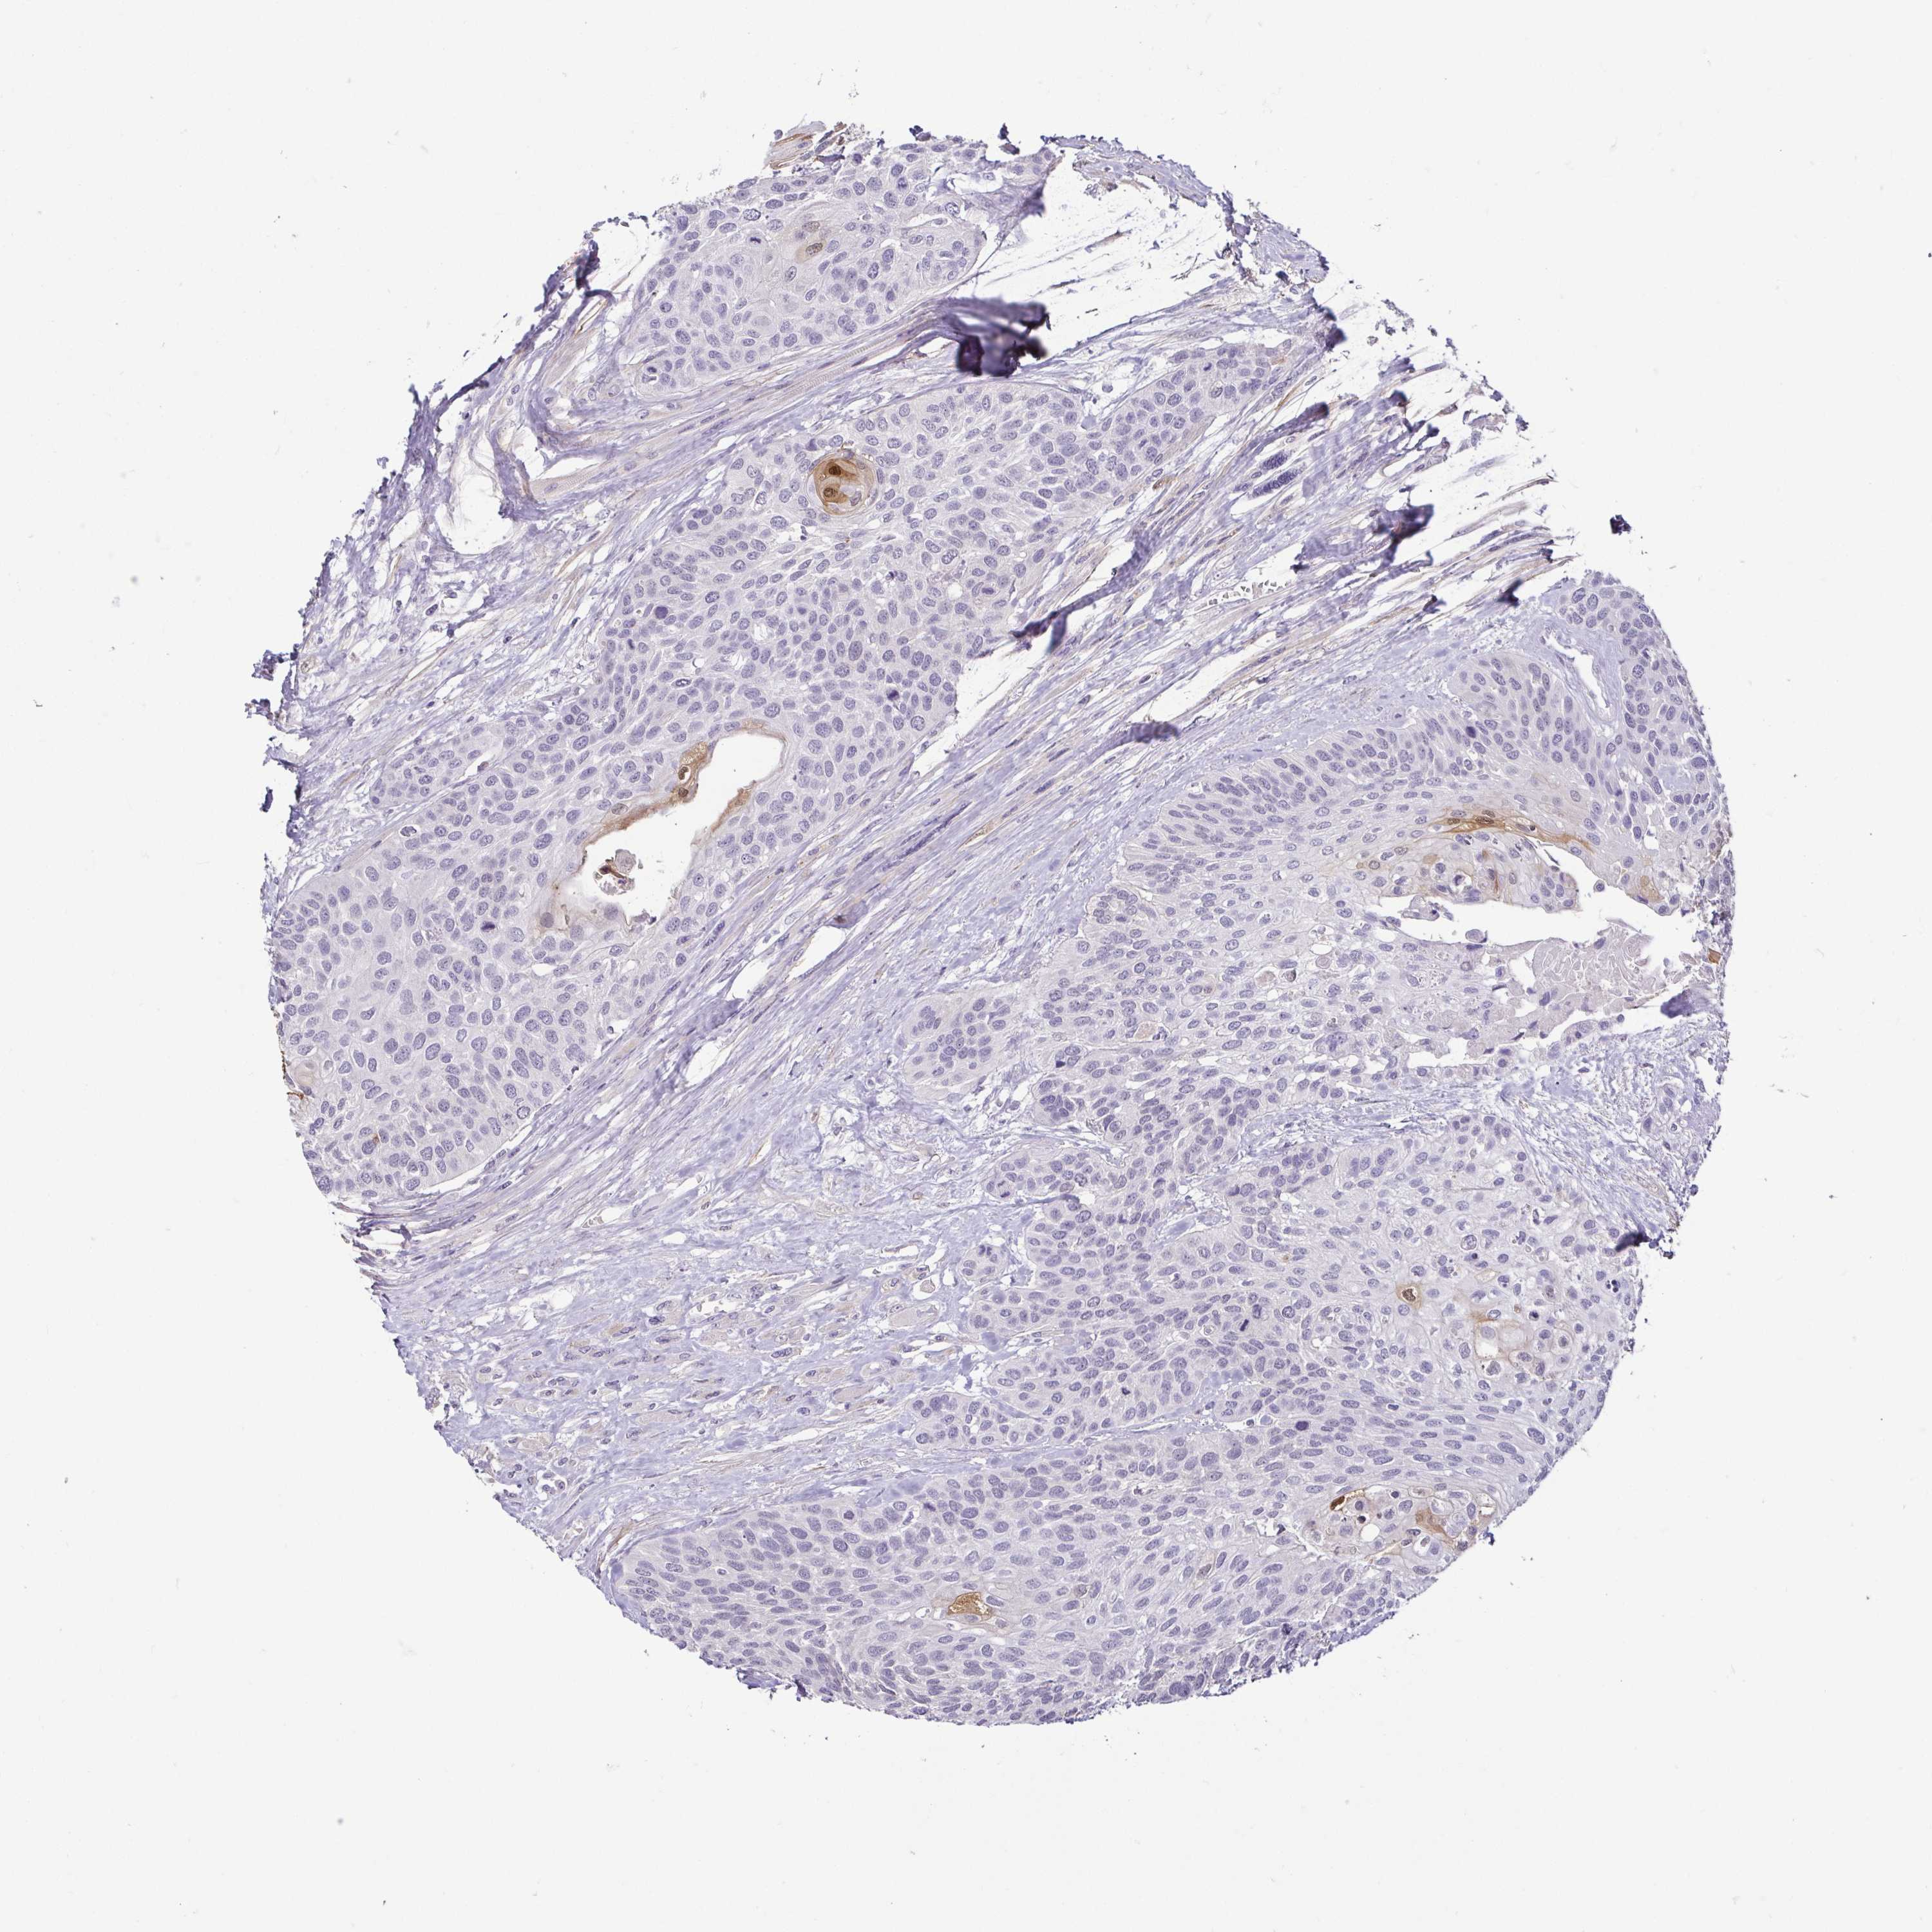

HEAD AND NECK CANCER - Protein expressioni

A mouse-over function shows sample information and annotation data. Click on an image to view it in a full screen mode. Samples can be filtered based on level of antibody staining by selecting one or several of the following categories: high, medium, low and not detected. The assay and annotation is described here.

Antibody stainingi

Antibody staining in the annotated cell types in the current human tissue is reported as not detected, low, medium, or high, based on conventional immunohistochemistry profiling in selected tissues. This score is based on the combination of the staining intensity and fraction of stained cells.

Each image is clickable and will lead to virtual microscopy that enables deeper exploration of all samples and also displays staining intensity scores, fraction scores and subcellular localization as well as patient and tissue information for each sample.

Antibody HPA030180

Antibody CAB018632

Staining

High

Medium

Low

Not detected

Intensity

Strong

Moderate

Weak

Negative

Quantity

>75%

75%-25%

<25%

None

Location

Nuclear

Cytoplasmic/membranous

Cytoplasmic/membranous,nuclear

Squamous cell carcinoma, NOS